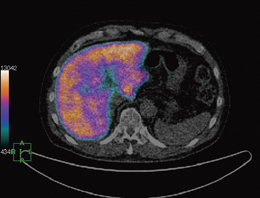

前述のとおり,高密度な医用三次元画像における肝臓機能評価は,主に体積を測定することで機能が推定されていた。しかし以前より,肝機能評価は,RI(放射性同位元素)を用いた測定が一般的であり,検出器や画像化アルゴリズムの進歩に伴い,現在も多くの検査がなされている。そこでわれわれは,医用三次元画像における上記の解析機能に,RIによる機能情報を付加することで,肝機能をさらに深く評価できる可能性を研究している。

しかし,前述のとおり,三次元画像として収集されるCTやMRIのデータに対して,SPECTなどのRIを用いた検査は機能画像と呼ばれ,一般的に形状情報に乏しく,また違うモダリティ,違う検査日で撮影されることが多い。そのため従来では,三次元データの肝臓部分に対して機能画像中の同一部位を重ね合わせることは,ほぼユーザーの目視によって判定され,定量性の低さを指摘されることが多かった。この問題を解決するため,当社は独自のアイデアに基づいた新しい非剛体レジストレーション手法を開発した(図3)。本手法により,以前より豊富なデータに基づく核医学の情報を,より治療に適した情報として抽出することが可能になると考えている。